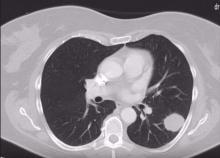

A 57-year-old patient was admitted for metachronous single metastases in the left lower lobe. The metastasis was located in the apical segment of the lower lobe and was 4.5 cm large. Three years prior, the patient had undergone rectum resection followed by adjuvant therapy. A uniportal videothoracoscopic posterior approach with a 4 cm single incision was used to avoid dissection through the fissure (especially as it may have been fused). The author also thought it reasonable to have all of the involved structures in front of the incision. The incision was made in the seventh intercostal space, behind the posterior axillary line. The patient had minor pain treated with non-steroid anti-inflammatory drugs in the postoperative period. The postoperative course was uneventful. The patient was discharged from hospital on the fourth postoperative day.